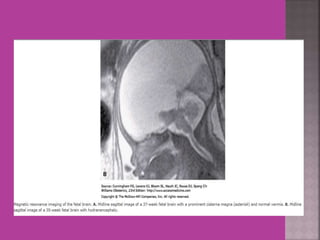

MRI Normal Fetal Brain at Term

MRI Normal FetalBrain at Term